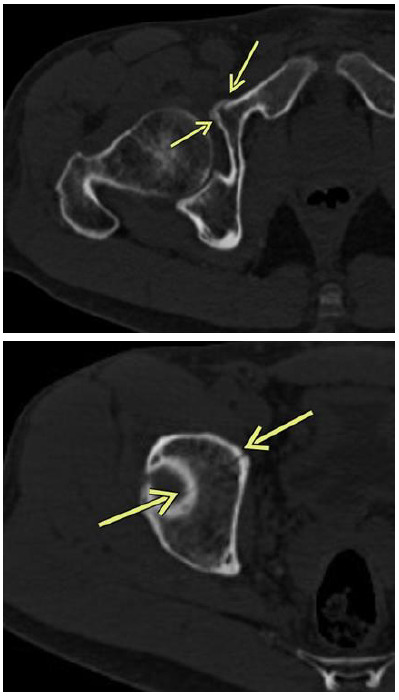

近几十年来,自行车作为一种交通工具和一项竞技运动的参与稳步增加。由跌落和碰撞引起的创伤性损伤发生的相对频繁。髋部和骨盆骨折并不常见,迄今为止没有研究报道其在这项运动中的确切发生率。髋臼特异性损伤的报道甚至更少。我们提出了四个病例,突出了骑自行车者髋臼骨折的隐伏性,并记录了他们的管理和恢复。从自行车上直接跌落到髋侧部导致髋臼骨折的数量相对较高。其中许多可能因x线平片未见发现而被遗漏。因此,在治疗与骑行相关的创伤性损伤时,高度怀疑髋部和骨盆骨折是很重要的。

Cycling participation as a medium of transport and as a competitive sport has steadily increased in recent decades. Traumatic injuries secondary to falls and collisions occur relatively frequently. Fractures of the hip and pelvis are uncommon with no studies to date reporting their exact incidence in this sport. Injuries specific to the acetabulum are reported even less frequently. We present four cases that highlight the insidious nature of acetabular fractures in cyclists and document their management and recovery. The number of acetabular fractures following falls from bicycles directly onto the lateral hip result in a relatively high number of fractures. Many of these may be missed due to the absence of findings on plain x-ray imaging.It is therefore important to have a high index of suspicion for hip and pelvis fractures when treating cycling related traumatic injuries.